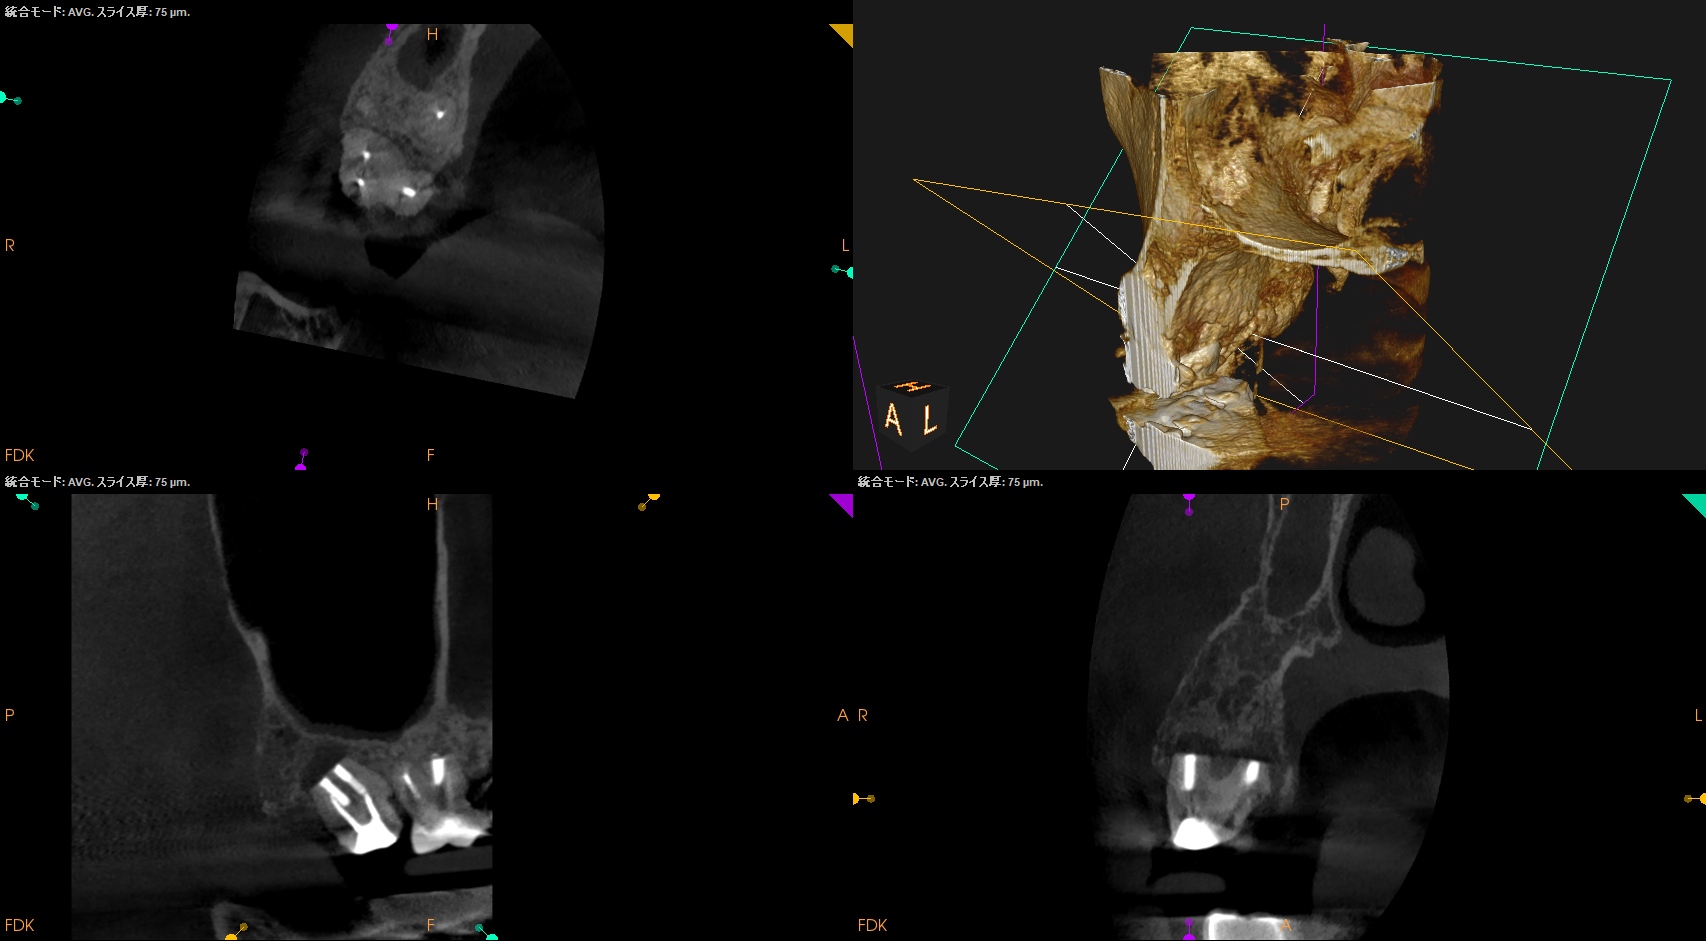

以前の治療の経過観察。

あれからさらに1ヶ月が経過した。

#2 Intentional Replantation 2M recall(2025.10.1)

痛みはないが若干、違和感がある程度に症状は軽減した。

臨床症状はないのでかかりつけ医の先生にはプロビジョナルレストレーションの装着を依頼した。